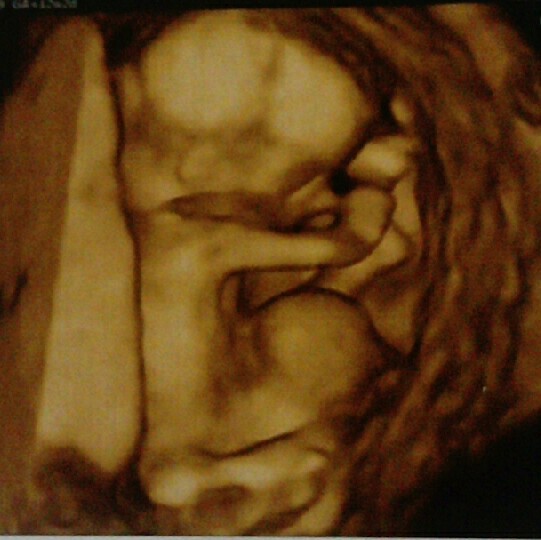

Czasem nir ma co sir martwić na zapas bo jak widzisz wszystko dobrzeCześć ale miałam trudny czas. Wczoraj zrobiłam betę i niestety przyrost był bardzo mały 31.08 beta 13900 a po tygodniu 7.09 30900, cała noc przepłakałam , dodatkowo plamie wiec już nastawiałam się na łyżeczkowanie , przeczytałam cały internet. Poszłam dziś do doktorka i wszystko jest pięknie , dzidziuś się dobrze rozwija , serduszko bije z usg 7t0d z miesiączki 6t6di tak oto ja schizolka

Zobacz załącznik 1173862